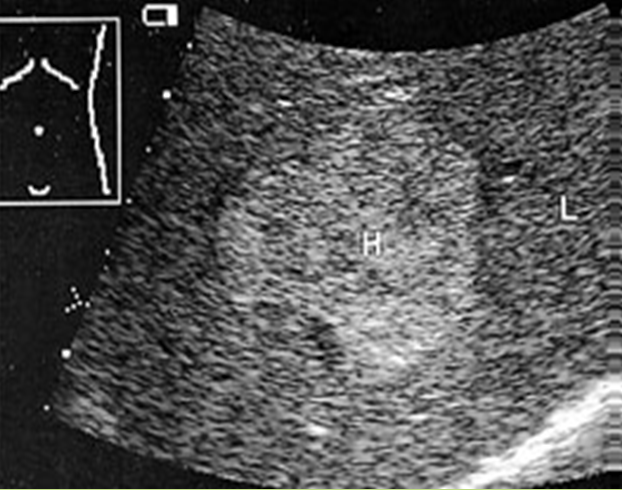

What is the sonographic appearance of Cirrhosis?

Hepatomegaly

Increased echogenicity and attenuation

Size

decrease of right lobe

Size increase of left and caudate

lobe

Nodularity

Fibrosis

Hepatospenomegaly

Ascites

Portal

hypertension

Hepatoma tumors

caudate lobe may be spared